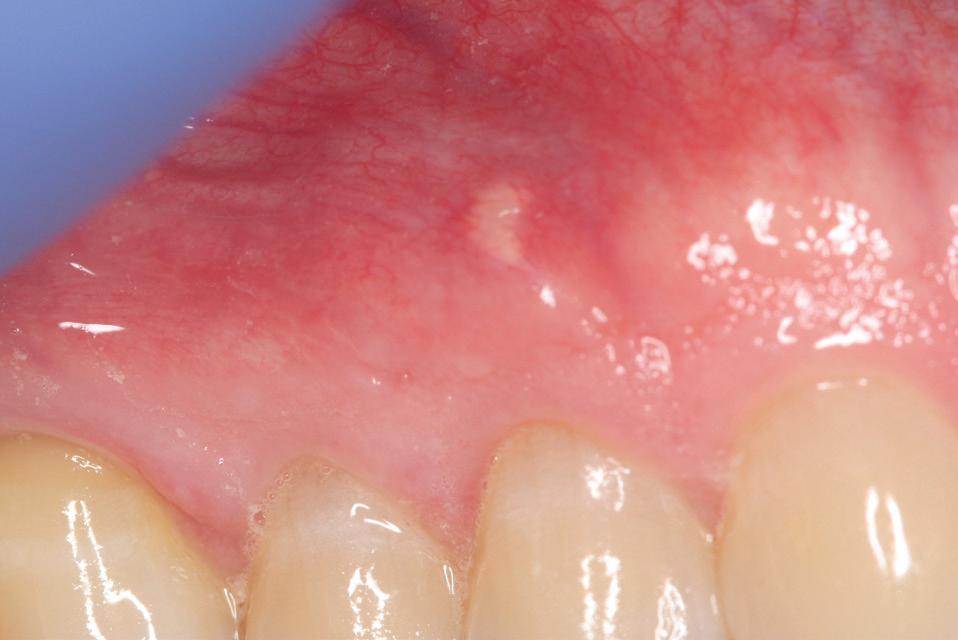

48 Oral Medicine, Oral Diagnosis, Oral Pathology

Multidisciplinary approach to diagnosis and management of lymphadenopathy in a patient with mucous membrane pemphigoid: a case report